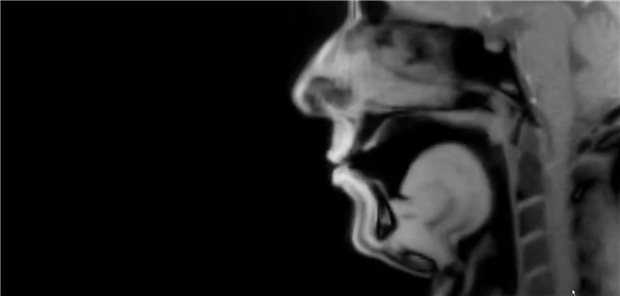

MRT-Aufnahme der inneren Sprechmuskeln eines 42-jährigen Patienten mit idiopathischem Stottern, während er einen Text vorliest.

© Screenshot: The Lancet / https://www.youtube.com/watch?v=a4lg7OPT9Ho

Blick auf die Sprechmuskeln

Echtzeit-MRT-Aufnahme eines stotternden Patienten veröffentlicht